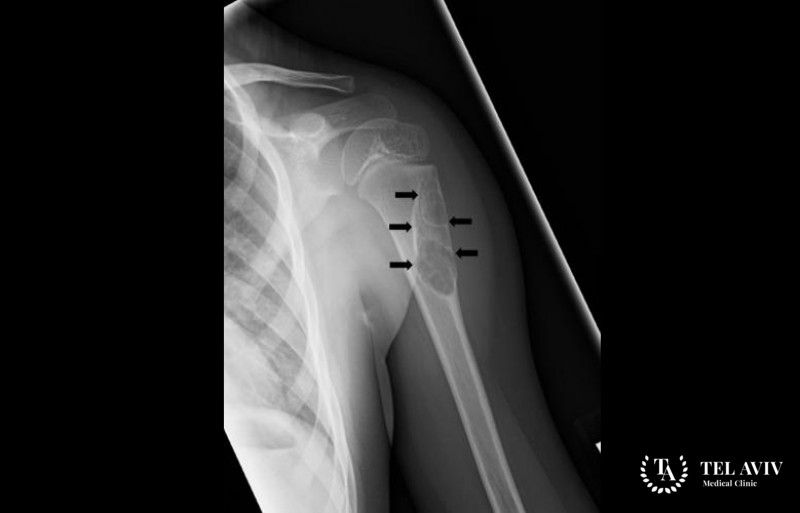

При подозрениях на наличие костной кисты пациента отправляют на рентгенографию. Такой метод диагностического исследования позволяет поставить точный диагноз. Во время лечения пациенту часто назначают рентген и УЗИ, это позволяет следить за течением заболевания и оценивать эффективность выбранного лечения.